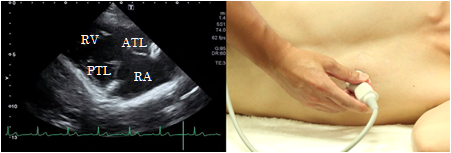

Longitudinal view of the right ventricular inflow tract

To obtain the longitudinal view of the right ventricular inflow tract, rotate the probe slightly in a clockwise direction from the longitudinal parasternal view of the left ventricle and tilt it so that the ultrasound beam is directed slightly downwardly. The anterior cusp of the tricuspid valve is visualized in front and the posterior cusp is visualized at the back. This view is suitable for observation of the tricuspid valve, right ventricle, and the right atrium and to estimate the right ventricular systolic pressure from tricuspid regurgitation.